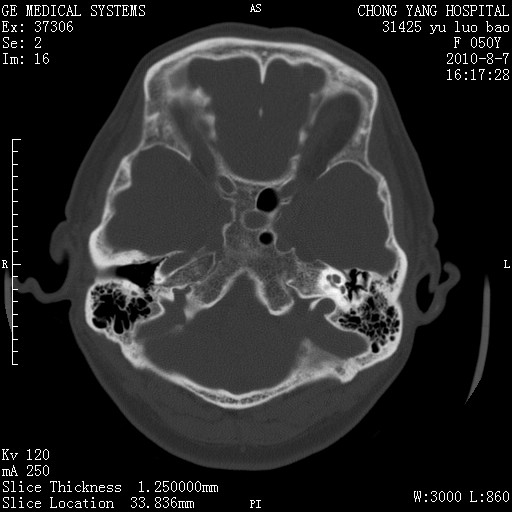

右侧桥小脑角去等密度占位,右侧内听道扩大、骨质吸收,考虑:右侧听神经瘤,建议增强检查。

右侧内听道扩大、骨质吸收,中脑受压左移,考虑:右侧听神经瘤,建议增强检查。支持!

骨窗示右侧内听道扩大,考虑右侧听神经瘤。

右侧桥小脑角区等密度占位,内耳道扩大,听神经瘤